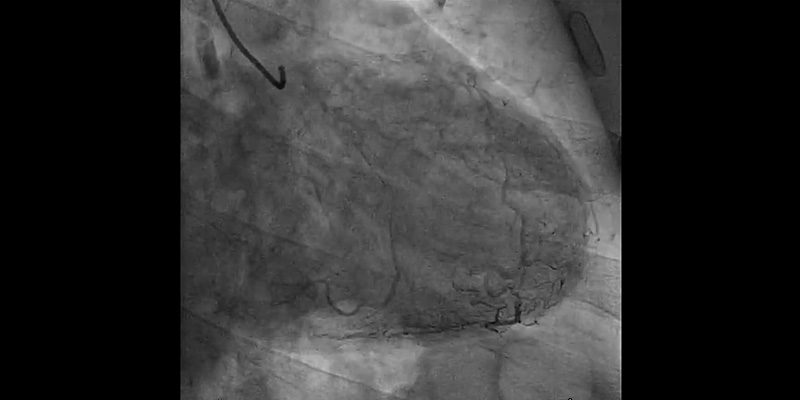

Coronary Angiography

• Right coronary artery showed significant stenosis in the proximal segment (70%), severe calcification of the proximal and mid segments, and critical stenosis in the distal segment (95%)

• LAD with stent in the proximal segment without restenosis. Mid LAD showed severe calcification with a significant stenosis - 85% (Medina 1-0-1) involving the diagonal ostium

• Circumflex artery: first obtuse marginal, 70% stenosis. Second obtuse marginal with implanted stent, without restenosis

Syntax score I: 20, Syntax score II PCI: 28.2, CABG 30.5.

• Control angiography showed dissection at bifurcation involving the ostium of the first diagonal branch. With the help of a dual-lumen catheter, a second wire was placed into the diagonal branch.